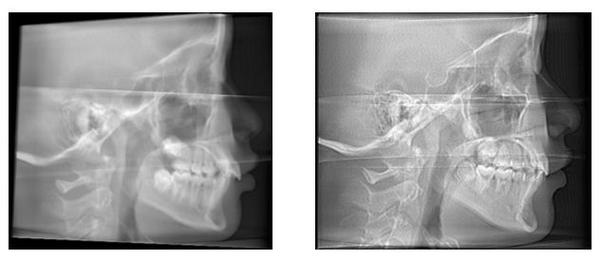

- 头部倾斜(歪头): 导致正中矢状面不垂直,左右结构不对称,所有角度测量(如ANB角)和距离测量出现偏差。

- 头部前倾或后仰: 改变颅底平面(FH平面)与地面的关系,影响颅颌面结构相对位置的判断,导致ANB角、SN-MP角等测量错误。

- 眶点(Or)与耳点(Po)未水平对齐: FH平面倾斜,导致所有基于FH平面的测量(如下颌平面角、Y轴角)不准确。